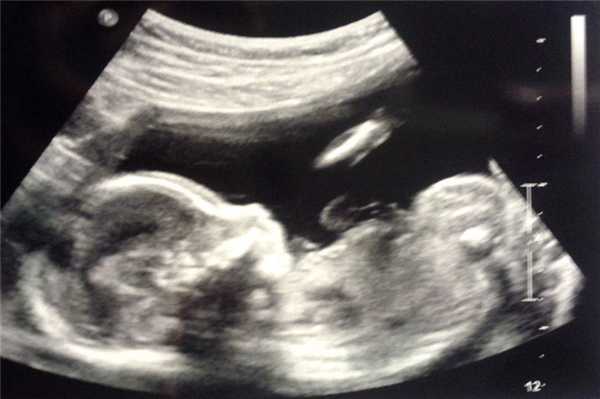

Фото УЗИ ребенка на разных сроках беременности

Если беременность желанная, будущие родители внимательно относятся к пренатальной диагностике плода. Чтобы убедится, что ребенок развивается нормально, в течение 9 месяцев гинеколог несколько раз направляет женщину на ультразвуковое исследование. Фото УЗИ может многое рассказать врачу и будущим родителям о малыше. Кроме того, снимок станет трогательным напоминанием для семейного архива.

Чтобы сделать фото УЗИ малыша на разных сроках, беременной женщине необходимо записаться на ультразвуковой скрининг в медицинском центре «Диана».